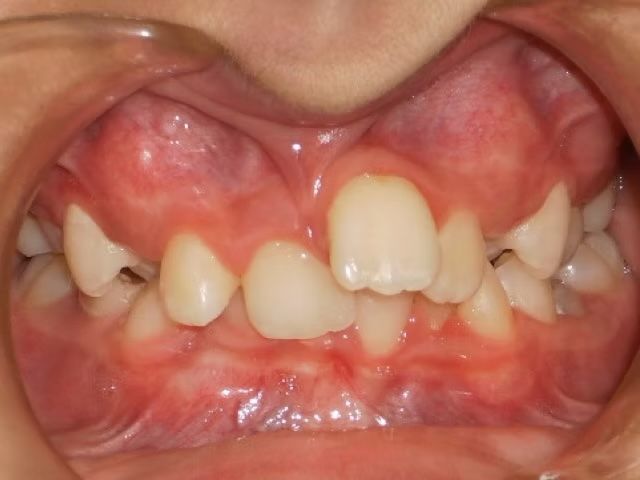

AUSTIN

Austin didn't like that his upper teeth fit behind his lower teeth. (He had an anterior crossbite). When this happens there are usually 3 ways to correct it. One way is just to move the top teeth forward, another is to take out teeth to help correct the crossbite, and sometimes and thankfully less common is to have jaw surgery to correct a skeletal size discrepancy between the top and bottom jaw. Dr. Bret was able to align Austin's teeth and correct his cross bite without taking out any teeth. Austin was super happy and loves his new smile.